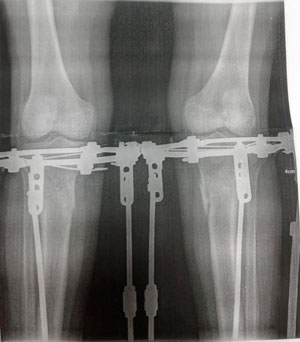

Исходник - 34 года.

Дата операции -- 03.07.2020

Дата снятия аппаратов 22.10.2020